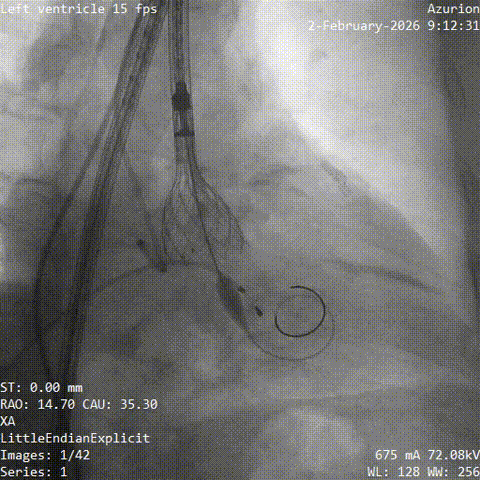

手术当天,团队顺利完成经导管主动脉瓣置换术。术中瓣膜释放位置理想,人工瓣膜功能良好,未见明显瓣周漏,也未出现严重传导阻滞、恶性心律失常等情况,患者术后安返CCU病房。

▲导丝跨瓣

▲18mm球囊预扩

▲输送器过弓

▲瓣膜定位

▲释放至工作位

▲工作位造影

▲脱钩

▲20mm球囊后扩

▲最终造影

术后复查显示,患者瓣膜功能改善明显,最大跨瓣压差较术前明显下降,峰值流速同步改善。术后第3天,患者已可在家属搀扶下下地活动,胸闷、头晕等症状较前缓解,随后顺利出院。